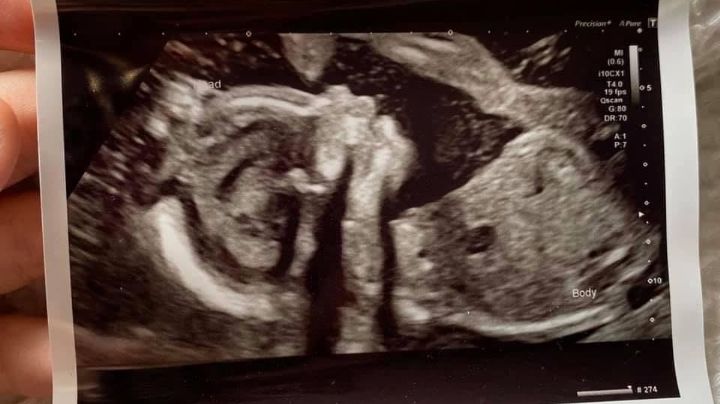

2/12/2021 | Con 14 votos a favor, cinco en contra y cuatro abstenciones, los legisladores del Congreso de Colima aprobaron una reforma a varios artículos del Código Penal y la Ley de Salud relacionados con la interrupción de la gestación